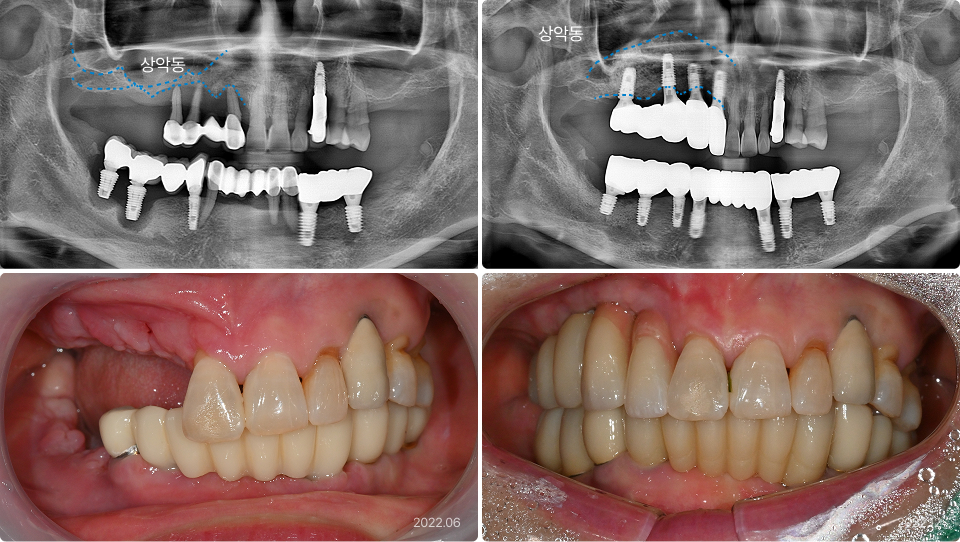

상악동 거상술 치료 사례

62세, 남

“위턱에 뼈가 하나도 없어서 임플란트를 못 한다고 했어요.”

치료 전

치료 후

• 상악동(빈 공간)이 커서 잇몸뼈가 1mm도 남지 않음

• PRF를 동반한 뼈이식, 상악동거상술로 안정적으로 잇몸뼈를

증가시킴